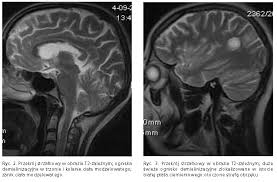

Badanie jest w zupełności bezpieczne. Sclerosis multiplex, sm) jest przewlekłą, autoimmunologiczną chorobą ośrodkowego układu nerwowego.objawia się stopniową degradacją osłonek mielinowych włókien nerwowych, co utrudnia przesyłanie impulsów pomiędzy nerwami. Czasami konieczne jest wykonanie punkcji lędźwiowej. Dwa jasne ogniska po lewej stronie odpowiadają obszarom demielinizacji p.grieb, l.królicki, wpaść w rezonans stwardnienie rozsiane jest jedną z najczęstszych przewlekłych i nieuleczalnych chorób neurologicznych, która na ogół diagnozowana jest między 20. Na stwardnienie rozsiane chorują ludzie do 50 roku życia, potem ryzyko zachorowalności spada. Rezonans magnetyczny głowy oraz kręgosłupa; Na podstawie przedstawionych przez panią danych tj. Diagnoza stwardnienia rozsianego rezonans magnetyczny. Przebieg choroby różni się u każdego człowieka, ale u większości występują okresy zaostrzenia choroby a potem następuje poprawa. U nas, chorych na sm, metoda ta potwierdza obecność ognisk demielinizacji, charakterystycznych dla stwardnienia rozsianego. Stwardnienie rozsiane uznawane jest za najczęstszy czynnik neurologiczny prowadzący do niepełnosprawności u ludzi w młodym wieku. Z przychodni odrazu mi powiedziala ze to stwardnienie rozsiane. Te zmiany chorobowe bywają niekiedy nazywane plakami.

W związku z zaistniałymi w procesie diagnozy problemami, naukowcy wciąż opracowują nowe kryteria. U nas, chorych na sm, metoda ta potwierdza obecność ognisk demielinizacji, charakterystycznych dla stwardnienia rozsianego. Obecnie mr stosuje się standardowo w diagnostyce sm, pozwala na potwierdzenie rozproszenia objawów choroby w czasie i przestrzeni. Choroba ma najczęściej przebieg wielofazowy, z okresami zaostrzeń i remisji. W polsce jest nas natomiast ok 46 tysięcy. Tomografia komputerowa i rezonans magnetyczny wspomagają wykrywanie zmian i monitorowanie choroby. Ja mialam w pierwszej kolejnosci zrobiony rezonans rdzenia kregowego, pani doktor neurolog z przycjodni mnie skierowala fakt ze i tak zrobilam go prywatnie bo za dlugi okres czekania i na podstawie wyniku tego wlasnie badania zostalam sjierowana do szpitala na dalsza diagnostyke i dr. Że pacjent choruje na stwardnienie rozsiane. Badanie to wymaga wykonania nakłucia lędźwiowego. Na dodatek czasem mam wrażenie, że jako taki „pozasystemowy pacjent z sm, mam problem z uzyskaniem skierowania na rezonans i ustawieniem się w kolejce. W celu postawienia takiej diagnozy, konieczne jest spełnienie ścisłych kryteriów. Objawów oraz wyniku badania rezonansu magnetycznego głowy nie można rozpoznać stwardnienia rozsianego. Dane pochodzą z atlasu sm.

Przy podejrzeniu stwardnienia rozsianego przeprowadza się badanie głowy metodą rezonansu magnetycznego, a czasami również odpowiedniego odcinka kręgosłupa. Tak , podobno stwierdzono , że hormon produkowany na początku ciąży , może być wykorzystany w terapii sm.nawet zaczęto pracować nad stworzeniem leku opratego o ten hormon.ale jeśli wszystko się uda , to będzie on dostępny za dobre parę lat. To 144 nowozdiagnozowane osoby w każdym miesiącu. Za pomocą rezonansu magnetycznego można wykluczyć inne choroby, które swoimi objawami i przebiegiem przypominają stwardnienie rozsiane. W diagnostyce stwardnienia rozsianego najczęściej wykonuje się badanie rezonansem magnetycznym (mri).